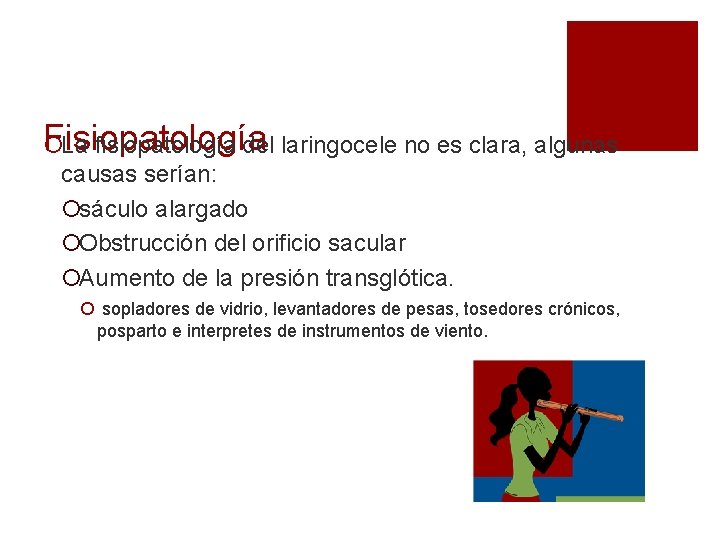

Fisiopatología ¡La fisiopatología del laringocele no es clara, algunas causas serían: ¡sáculo alargado ¡Obstrucción del orificio sacular ¡Aumento de la presión transglótica. ¡ sopladores de vidrio, levantadores de pesas, tosedores crónicos, posparto e interpretes de instrumentos de viento.